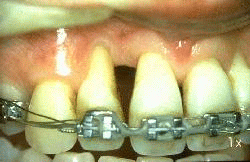

La imagen muestra 6 meses después del tratamiento. El paciente presenta una excelente higiene oral y al sondaje del surco gingival no presenta sangrado y evidencia una profundidad de 3 mm como máximo.